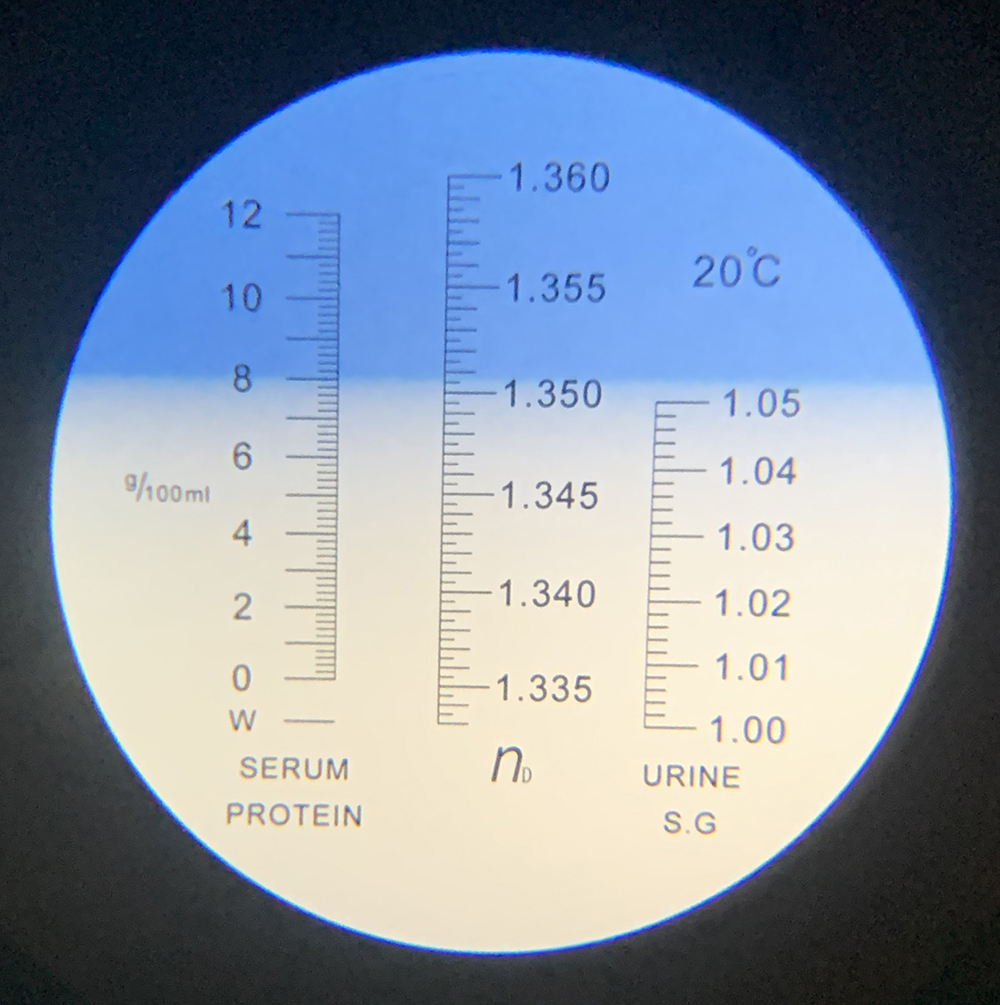

Diagnostiek

Het stellen van een diagnose kan soms net spoorzoeken zijn. Soms is het eenvoudig en soms is het lastig.

Onze diagnostische mogelijkheden hebben we uitgebreid door de aanschaf van vele soorten van apparatuur en het volgen van allerlei cursussen.